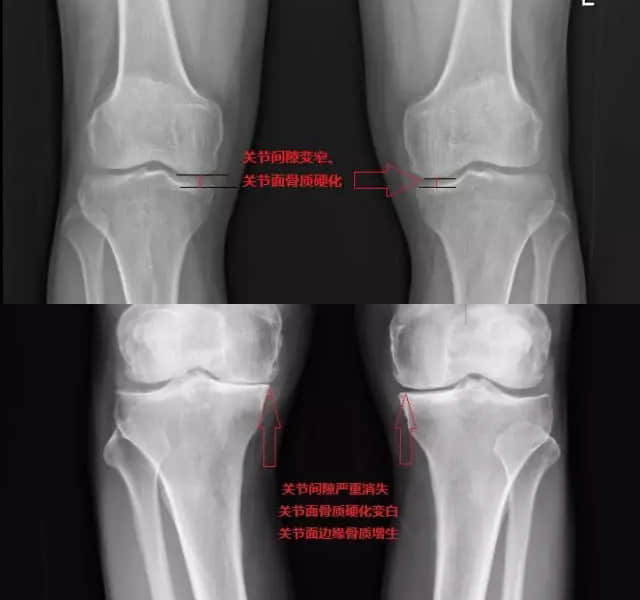

而在膝关节负重正位X线片上,常可以看见膝关节间隙变窄,关节表面骨质硬化变白,关节面边缘骨质增生、骨赘形成等等,膝关节免费拍片检查>>

我们一般首先会寻找膝关节骨性关节炎的表现标志,比如摩擦音——在活动膝关节时可能会感觉到这种声音。还有就是有的患者膝关节会出现肿胀或感觉到膝关节发胀。发胀是由于炎性关节液在膝关节里面积聚导致的。膝关节X线片可以发现膝关节间隙变窄,可以发现骨赘,还有异常的骨过度生长。这都是和膝关节软骨磨损和关节润滑液减少有关。